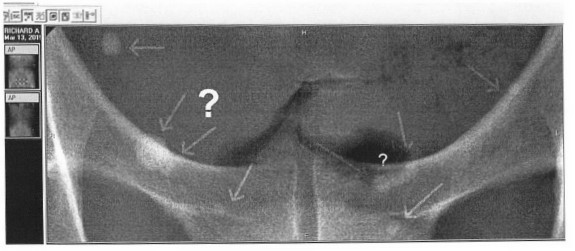

Right Photos are my arteries and are links, yikes! What does artery disease look like on a CTA? A 2017 CTA photo of my arteries: The left photo unfortunately shows the current disease in the CFX artery. My recent radiological report from these photos mentions coronary artery disease only and depicts the stenosis within the artery as a percentage, mine is < 25% great, but this is only a guesstimate and can vary 10% 20% and up to 30% is my understanding. I have seen two cardiologists since with the radiological report and they both say great less than 25%, blockage while neither actually even bothered to look at the photo with the actually disease. I asked both doc's if they would like to see the photos and they both declined. The Stenosis reported in the above angio photo group (BEFORE / AFTER) at the time of the stent was reported as 40% 50% and 60% by angio cath and now by CTA they say < 25%, I am in the process of finding out by comparison if this is true, I will be comparing the 2013 CTA to the 2017 CTA. By observation I noticed the overall sublumenal disease show in photos has not seemed to change much if at all. I also learned that the angio photo guesstimates are just that and do not hold much weight as far a accuracy if at all, they appear to be visual guides with numbers attached by the surgeon and or helper at the time of the CATH, why bother except to sell more operations. So in 2013 my artery blockages were 40-50-60% determined by the angiogram now compared to a CTA they are less than 25%, yea right, wishful thinking for sure. The disease looks the same to me photos to be posted. Can't help thinking that they do many unnecessary by pass operations based on the CATH readings/photos which are at best only guesstimates in most cases. i.e. I recently had a friend diagnosed by CATH that he had 80% blockages is all four arteries and received an immediate quadruple by bass operation? When you go under you basically give them cart blanche to do what is necessary, the way I got around this was to get the CTA before the CATH, In my case I was pretty sure what was going to happen before the CATH.

In the above left photo white is calcified plaque, dark irregularities and raised areas are the disease itself . Of note: although the stenosis, narrowing is only 25% this give or take 10% -30%, yes. in most cases it is reported that the stable white plaque is not the soft vulnerable plaque that causes a heart attacks but instead its the dark areas of soft vulnerable plaque beneath the artery walls that tend to be the culprits, however they actually can occur anywhere at anytime. The idea is that through (positive remodeling) the plaque builds up pressure beneath the artery wall and finally when enough pressure or disease happens within, the area is subject to rupture. If the artery blockage us severe enough a heart attack can ensue. So passing all your basic yearly tests really don't mean a thing buddy, imaging is key! |

CTA Imaging for heart disease using a 640 Slice CTA 7. From the 3 photos below you can see kinda see the clarity that the 3 different types of imaging I had done and what each machines produces, unfortunately I still see my disease in the 3rd and best picture, so in 4 years the plaque burden evidently remains about the same, so good news. |

2013, CTA of my CFX |

2015 MRA of my CFX artery MRI machine |

2017, 640 CTA slice machine of my CFX artery Dr. Amar Shah location of Northwell CTA |

2020 curved multi planar images showing stent in LAD(left) and disease in LCX tks Dr. Shaw for great images, end view of arteries are seen on right. |